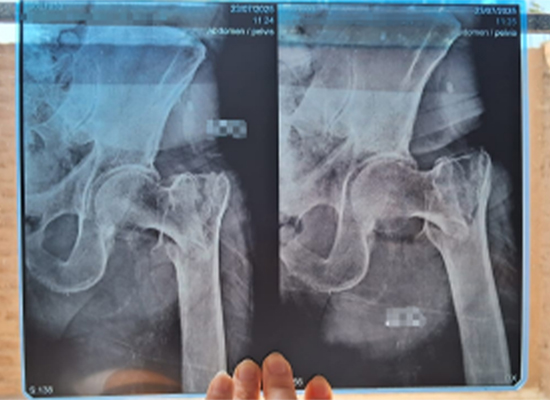

Рентгенологическое исследование подтвердило перелом левого межвертельного отдела со смещением , требующий своевременного хирургического вмешательства для восстановления стабильности и подвижности.

Предоперационная рентгенограмма, показывающая межвертельный перелом слева со смещением у пожилого пациента, Лима, Перу.